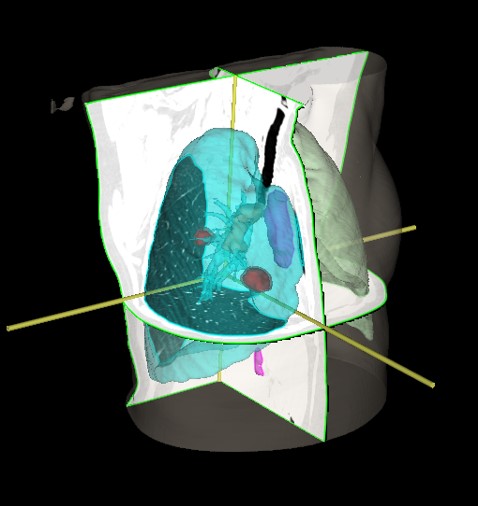

SABR meta pulmonum bilateralium (06/2017, 11/2019, 11/2020, 03/2021, 01/2022, 9/2023)

SABR meta pulm. et costae VIII l. sin. (5.4. – 6.4.2023.)

Volumna regresija tretirane lezije za 31.2%

Volumna regresija tretirane lezije za 88.4 %